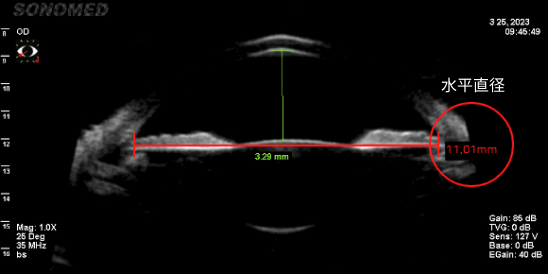

只有准确测量眼内空间是否足够,才能确定能否手术、晶体尺寸、可最小化晶体旋转概率的植入位置。

由于垂直直径平均比水平直径长,因此垂直型V-Toric ICL是在宽敞的空间内植入尺寸适中的晶体,晶体不接触周围组织,预防了晶体植入手术的副作用并提高了稳定性。

• 水平眼内空间测量(11.01mm)

• 垂直眼内空间测量(11.22mm)

垂直直径空间更广